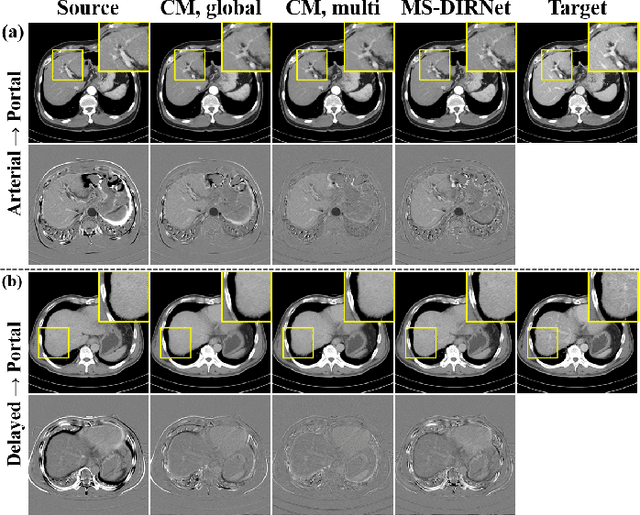

Image registration is a fundamental task in medical image analysis. Recently, deep learning based image registration methods have been extensively investigated due to their excellent performance despite the ultra-fast computational time. However, the existing deep learning methods still have limitation in the preservation of original topology during the deformation with registration vector fields. To address this issues, here we present a cycle-consistent deformable image registration. The cycle consistency enhances image registration performance by providing an implicit regularization to preserve topology during the deformation. The proposed method is so flexible that can be applied for both 2D and 3D registration problems for various applications, and can be easily extended to multi-scale implementation to deal with the memory issues in large volume registration. Experimental results on various datasets from medical and non-medical applications demonstrate that the proposed method provides effective and accurate registration on diverse image pairs within a few seconds. Qualitative and quantitative evaluations on deformation fields also verify the effectiveness of the cycle consistency of the proposed method.